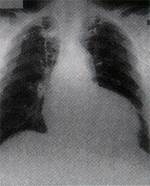

心 肌 肥 厚 或 放 大 |

急 性 肺 水 腫 |